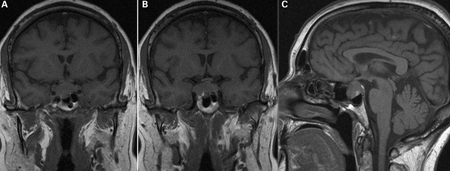

[Figure caption and citation for the preceding image starts]: A) Coronal T1 weighted magnetic resonance imaging (MRI) scan showing a pituitary mass with expansion of the pituitary fossa. (B) Coronal T1 weighted MRI scan showing a pituitary mass extending into the cavernous sinus, particularly on the right. (C) Sagittal T1 weighted MRI scan of the pituitary tumourBMJ Case Reports 2009; doi:10.1136/bcr.08.2009.2193 [Citation ends].